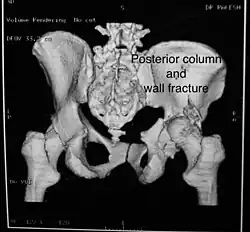

Posterior column As with posterior wall injury, this also typically occurs due to dash board injury. Posterior column + Posterior wall These fractures are extensions of elementary fractures. With the involvement of the posterior wall, the difficulty in treatment increases. These fractures are rarely amenable to non-surgical treatment. Due to posterior wall fracture, the hip is usually dislocated posteriorly, requiring immediate reduction of dislocation and surgical reconstruction after a few days.

The posterior column with posterior wall fracture occurs due to dashboard injury. The anteroposterior view may give clues to these injuries. Judet views and CT scans help in knowing the extent of the injury.